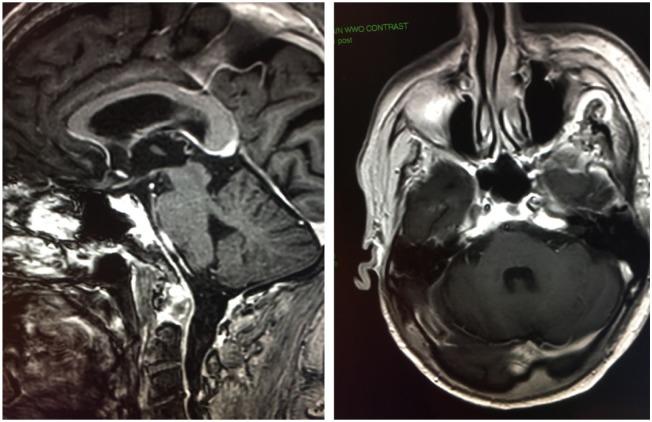

A 72-year-old gentleman presented with facial neurological deficits and a dermal nodule and was diagnosed with spindle cell squamous cell carcinoma with perineural invasion. His course was notable for early intracranial metastasis with progressive neurological deficits despite recurrent radiation therapy with intermittent response. When progressive left-sided weakness prompted imaging evaluation that was concerning for disease recurrence after exhaustion of radiation therapy options, the patient was started on systemic therapy with the anti-PD-1 monoclonal antibody treatment prior to the approval of cemiplimab. Pembrolizumab was chosen due to the fact that the patient was ineligible for clinical trials and for its every 21-day dosing. With this treatment, he has achieved a durable clinical response, resulting in near resolution of neurological deficits and more than a year of progression-free survival to date, despite aggressive intracranial disease.

一名72岁男性患者出现面部神经功能缺损和一个皮肤结节,被诊断为伴有神经周围侵犯的梭形细胞鳞状细胞癌。他的病程特点是早期颅内转移,尽管反复进行放射治疗且有间歇性缓解,但仍出现进行性神经功能缺损。当进行性左侧肢体无力促使进行影像学评估,提示在放射治疗方案用尽后疾病复发时,在西米普利单抗获批之前,该患者开始接受抗PD-1单克隆抗体的全身治疗。选择派姆单抗是因为该患者不符合临床试验条件,且其给药周期为每21天一次。通过这种治疗,他获得了持久的临床缓解,神经功能缺损几乎完全缓解,至今已无进展生存超过一年,尽管颅内疾病进展迅速。